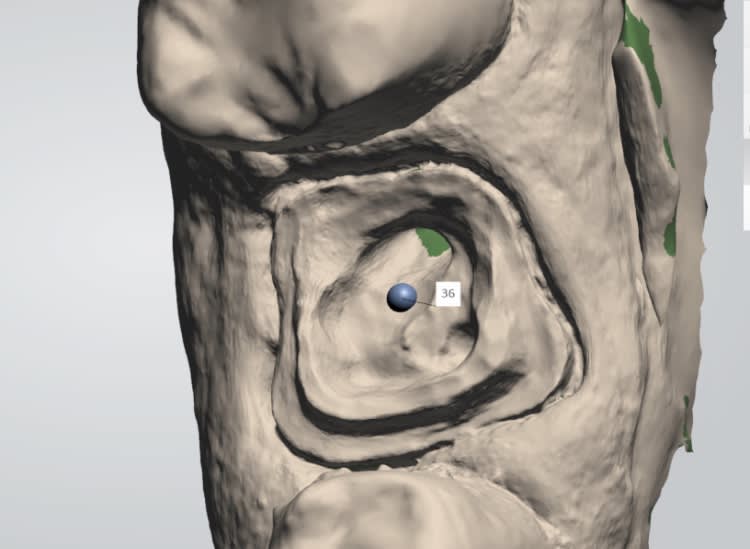

Vue platre.

Une autre.